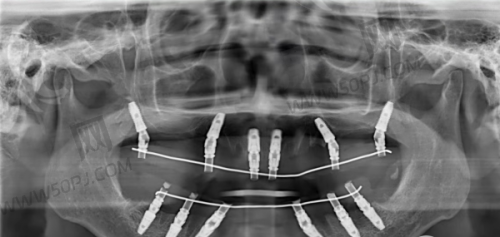

项目参考价格:种植牙3000元起,韩系种植3500元起,全口种植约10万起。

成功实例:邻居王阿姨原来怕假牙松动,这次在牙世佳做了五颗种植,医生每天跟进,每月复查一次,如今吃牛排都轻松。